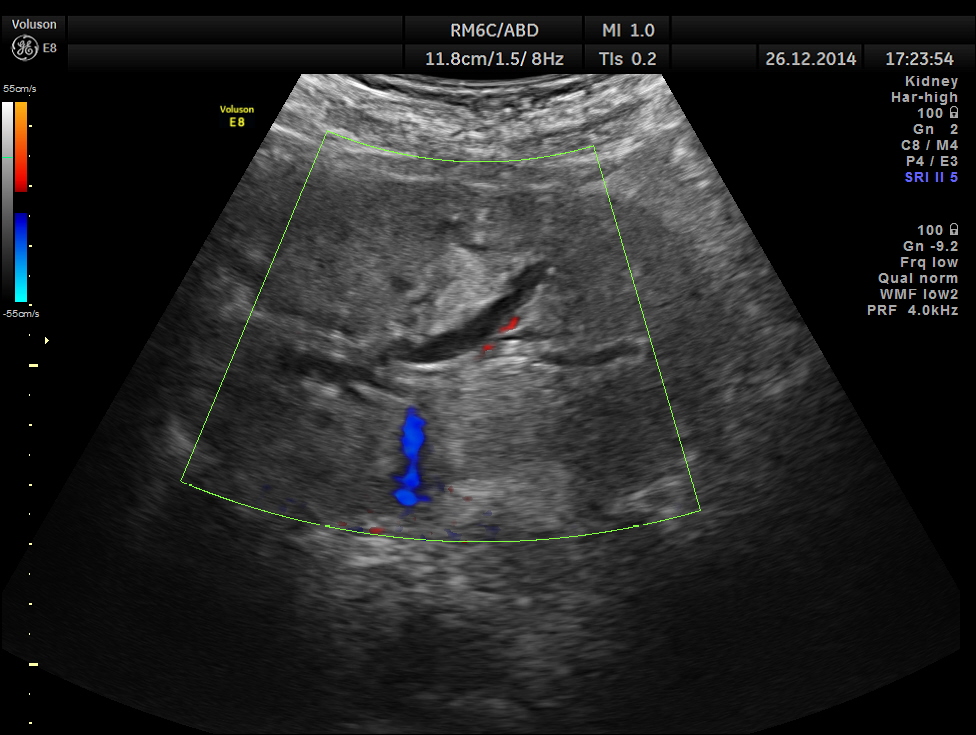

dilated pancreatic duct is seen